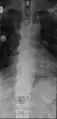

| DISH in an 80 year old female, also with T11 fracture. | |